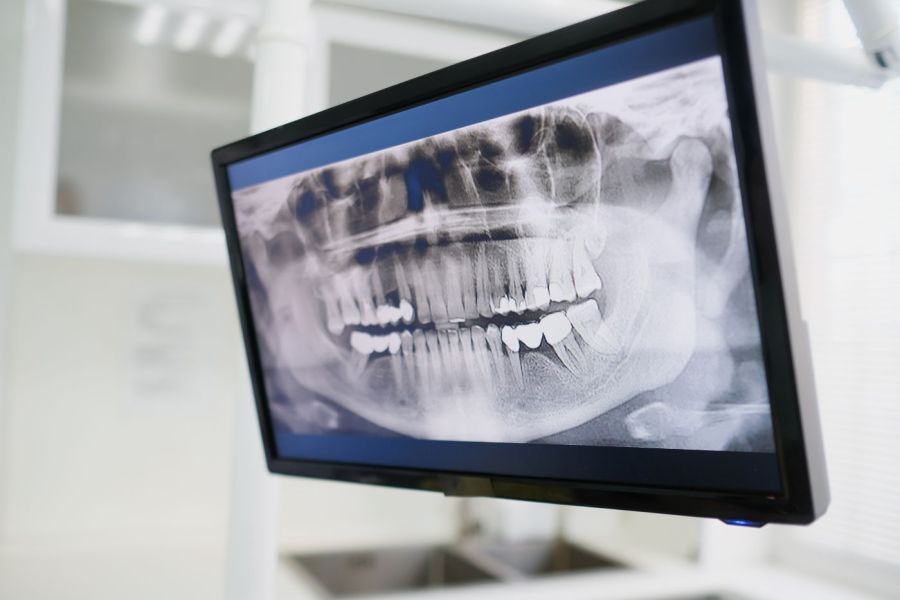

Zu Beginn analysieren wir den betroffenen Zahn und erstellen Röntgenaufnahmen, um Verlauf und Anzahl der Wurzelkanäle genau zu bestimmen.